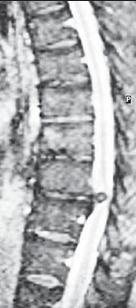

На МРТ № 28 наблюдается секвестрированная грыжа межпозвонкового диска в поясничном отделе позвоночника в сегменте LV—S1 с каудальной миграцией секвестра Межпозвонковые грыжи весьма опасны и коварны, даже если и не вызывают болей. Дело в том, что длительное раздражение или сдавление межпозвонковой грыжей задней продольной связки, оболочек спинного мозга вызывает развитие воспалительных процессов в спинномозговом канале с последующим развитием эпидурита (воспаление клетчатки эпидурального пространства), арахноидита (воспаление паутинной (арахноидальной) оболочки головного или спинного мозга), а так же спаечных процессов. Так что оставлять человека один на один с его проблемой «немых» грыж, не оказав ему своевременную помощь, это всё равно, что обрекать его на усугубление патологических процессов в его позвоночнике и развитие нового «букета» заболеваний. Хотелось бы затронуть и тему нейроинфекции. Профессор, академик Валентин Иванович Покровский (крупный ученый с мировым именем, клиницист-инфекционист, эпидемиолог) дал такое определение нейроинфекций: «Нейроинфекции — чрезвычайно гетерогенная группа распространённых заболеваний центральной и периферической нервной системы, характеризующихся, как правило, тяжёлым течением, высокой летальностью и стойкой инвалидизацией». В повседневной практике мне часто приходится встречаться с развитием нейроинфекции у больных, появившейся вследствие дегенеративно-дистрофических изменений в позвоночнике. В общем-то это естественно, так как, к примеру, длительное сдавление грыжей межпозвонкового диска оболочек спинного мозга или спинномозгового корешка вызывает развитие воспалительных процессов и приводит к эпидуриту, а порой и к арахноидиту. В свою очередь это обеспечивает идеальные условия для проникновения через очаг воспаления различных инфекционных агентов, особенно вирусов (от лат. virus — «яд»), которые таким образом, минуя гематоэнцефалический барьер, попадают непосредственно в спинномозговую жидкость (ликвор) и беспрепятственно распространяются по ликворным путям. А если при этом у больного имеется нарушение ликвородинамики вследствие сдавления ликворных путей грыжей межпозвонкового диска или же костными структурами позвоночника, что приводит к затруднению (замедлению) циркуляции ликвора и образует его длительные застои в нижней люмбальной цистерне (в пояснично-крестцовом отделе позвоночника), в боковых карманах спинномозговых корешков, то это в свою очередь вызывает нарушение питания тканей и обеспечивает идеальные условия для развития инфекционного процесса. А, как известно, инфекционный процесс составляет основу развития инфекционных заболеваний, по мере прогрессирования которых возникают значительные поражения спинного и головного мозга, нарушающие работу органов и систем организма. |